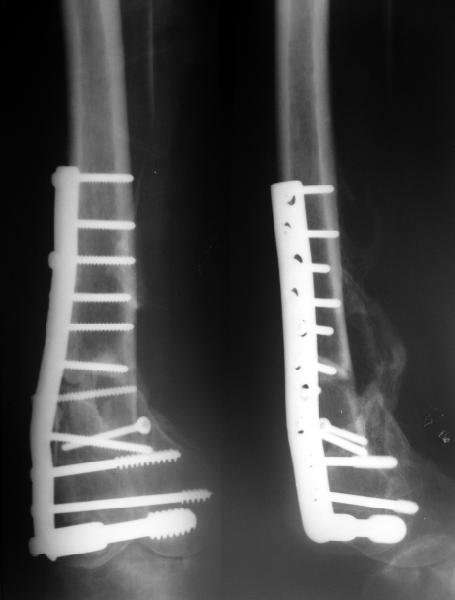

Мужчина 48 лет получил перелом бедра в IX 2003, оперировали в г. Одинцово, остеосинтез DCS.

A male 48 years old referred to us from another town. He sustained T-shape fracture of the distal femur (a car accident) in Sep. 2003, fixed by DCS somewhere else. The wound had some problems and healed completely to Dec. 2003. Since Jan 2004 started to bear wight with crutches, marked appearance of deformation. Now clearly some mobility is present, though the plate and screws look not broken. Knee ROM is 90 degrees. Your opinion about how to manage the case would be greatly appreciated.

It looks as if one screw was almost through the fracture site, now fracture seems to going into hypertrophc nonunion with loosening and backing up of plates from condyle.

The radiographs show an apex lateral (varus) deformity (about 10 degrees) at the distal femoral metaphysis fracture site with a bent plate. The fractures are only partly healed. The joint surface appears congruous.

Please expand upon your observation of "marked appearance of deformation". What deformity and how much? A lot of varus? Other?

"clearly some mobility" Is there motion at the fracture site to manual stress? Other?

Is the deformity new or progressive or was this fixed in this position?

If there is gross motion at the fracture site and gross clinical varus deformity then I would suggest removal of the loose/bent plate and restabilization with (order of preference) a locking plate, retrograde IM nail, a blade plate, a new DCS, ring XF, endosteal subsitution plate. I would add autologous cancellous bone graft.